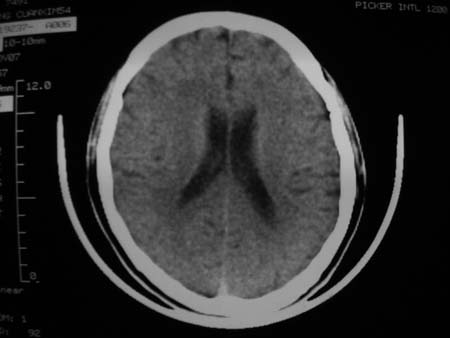

男,54岁,十天前被钢管打伤头顶部,现自述头部不适,视物模糊,并于两天前发觉右枕部有包块,既往未有明显异常.

颅骨多处骨质不完整,内板变薄,右侧额颞部局部呈“穿凿样”骨质缺损,相应区硬膜外密度略增高。多考虑:骨嗜酸性肉芽肿!

颅骨多处骨质不完整,内板变薄,右侧额颞部局部呈“穿凿样”骨质缺损,相应区硬膜外密度略增高。多考虑:骨髓瘤或骨嗜酸性肉芽肿!

颅骨多处骨质不完整,内板变薄,右侧额颞部局部呈“穿凿样”骨质缺损,缺损骨质边缘锐利无硬化,相应区硬膜外密度略增高。多考虑:骨嗜酸性肉芽肿!

颅骨多处骨质不完整,内板变薄,右侧额颞部局部呈“穿凿样”骨质缺损,相应区硬膜外密度略增高。多考虑:骨髓瘤或骨嗜酸性肉芽肿!10天前受伤,不会在2天前才发现头部包块,估计与外伤无关.